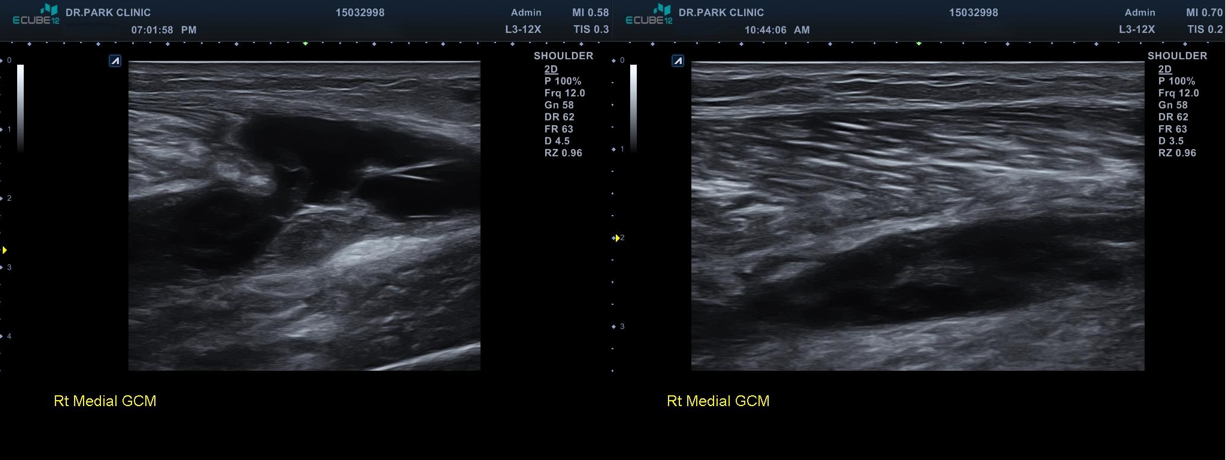

근육 파열이 훨씬 심해지고 근막이 다 벌어지면서 피가 고여있는 모습을 보이고 있습니다.